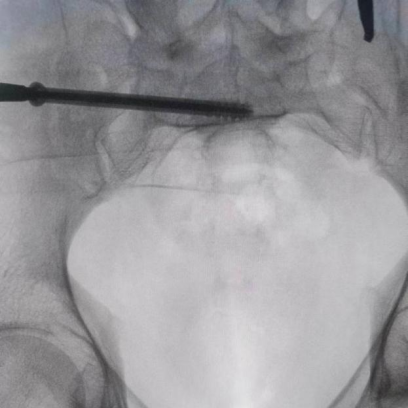

據(jù)了解,患者37歲,為高墜傷患者,入院合并顱腦挫傷、盆腔臟器出血、骨盆骨折多發(fā)傷患者。為最大限度降低手術(shù)風(fēng)險(xiǎn),同時(shí)給予患者滿(mǎn)意的手術(shù)療效,術(shù)前綜合評(píng)估患者病情,擬定行“天璣機(jī)器人”輔助定位下骨盆骨折微創(chuàng)手術(shù)。2月13日10時(shí),手術(shù)正式開(kāi)始。拉薩市人民醫(yī)院采集患者術(shù)中二維影像,通過(guò)骨科手術(shù)機(jī)器人擬定螺釘打入位置方向后,吳宏華主任完成手術(shù)設(shè)計(jì),成功為該患者置入了一顆高難度骶髂螺釘,出血5ml,切口1cm。術(shù)后圖像顯示,螺釘位置及方向完全符合手術(shù)規(guī)劃,沒(méi)有一絲偏差,手術(shù)最終獲得圓滿(mǎn)成功。

圖為透視下見(jiàn)置入的骶髂螺釘,位置、長(zhǎng)度精準(zhǔn),無(wú)絲毫偏差